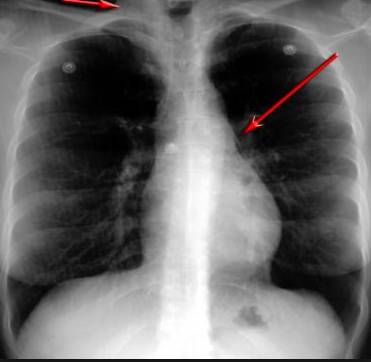

并且,因?yàn)楹粑到y(tǒng)結(jié)構(gòu)復(fù)雜,在體檢時(shí)醫(yī)生很難通過一種檢測(cè)手段,判定早期患者的病情。

把整個(gè)肺部看得清清楚楚!

使用這臺(tái)掃描儀,將直接把器官變成3D圖形!細(xì)微的毛細(xì)血管,幾毫米大的肺泡和支氣管,都將能看的一清二楚!

你的每一個(gè)氣泡,每一段支氣管,哪兒有病變都清清楚楚的將展示在醫(yī)生面前!

也就是說在一切都還沒開始惡化前,把這些有問題的器官組織都暴露的一清二楚:

沒有這項(xiàng)新技術(shù),醫(yī)生在做體檢的時(shí)候,很難通過一種測(cè)試斷定一個(gè)人是否有呼吸系統(tǒng)疾病。

可是現(xiàn)在他們不但能看到整個(gè)肺部的3維結(jié)構(gòu)圖。還能看到空氣進(jìn)入人體后的所有微小變動(dòng)!